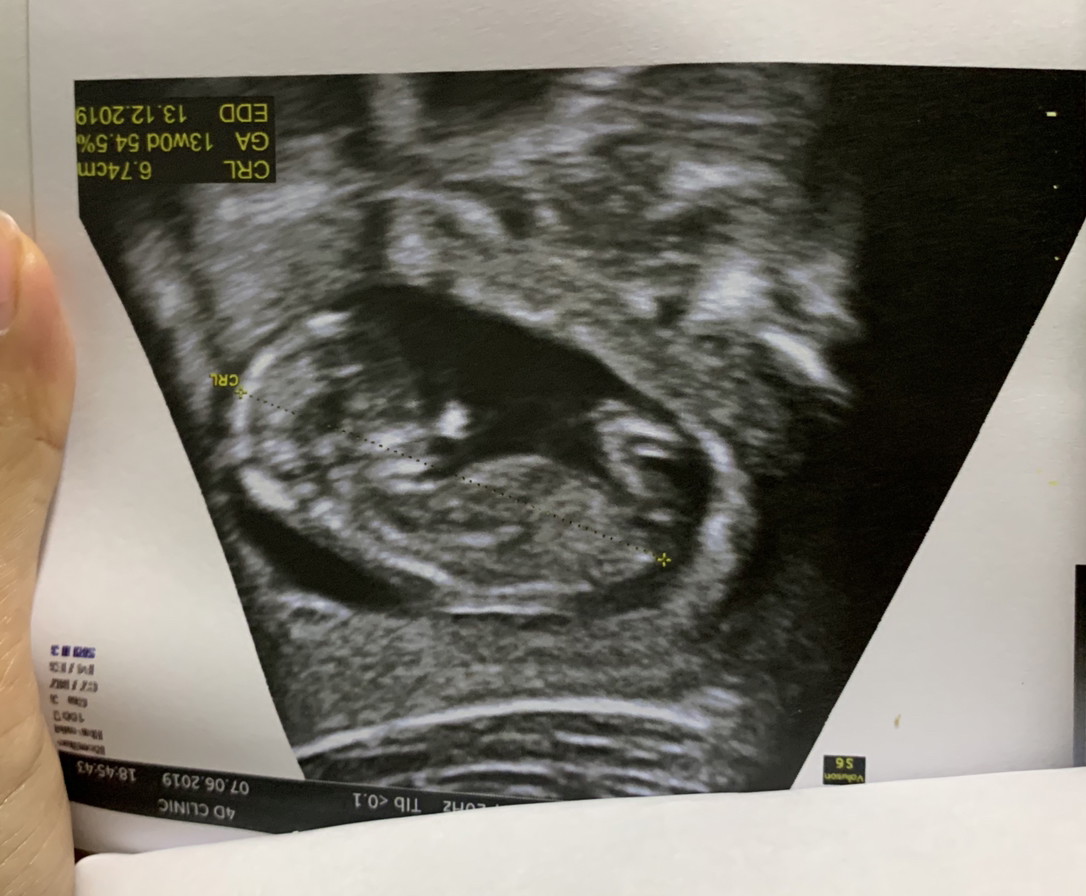

ตอน13weekคะ ตอนนี้19weekแล้ว

13w5d ค่ะ ตอนนี้ 16w1d